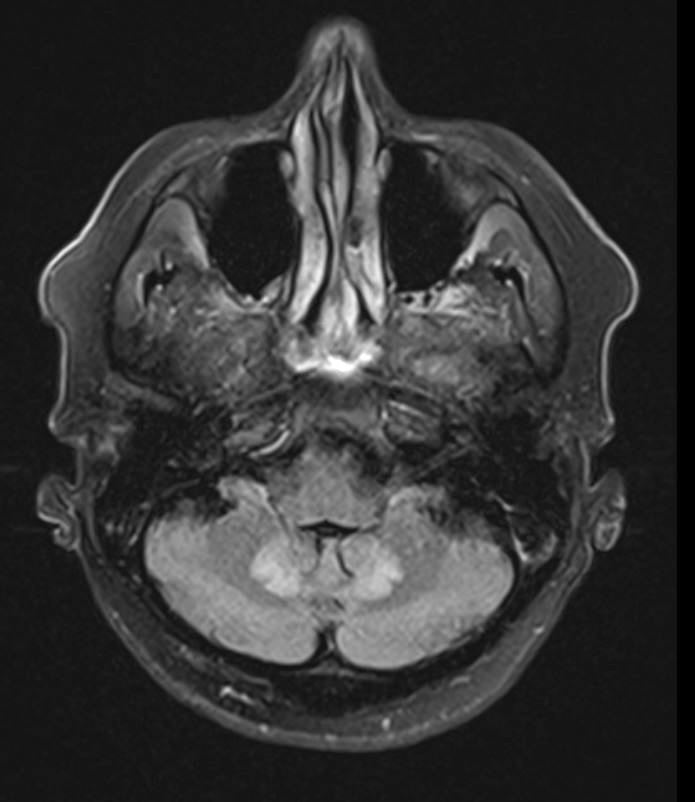

A computed tomography (CT) scan showed an age-indeterminant lacunar infarct in the pons. For diagnostic clarity, magnetic resonance imaging (MRI) of the brain was ordered, the results of which showed symmetric increased T2-weighted fluid-attenuated inversion recovery (FLAIR) signal within the dentate nucleus, periaqueductal gray, tectum, red nucleus, and splenium of the corpus collosum, consistent with toxic acquired metabolic encephalopathy (Figures 2 and 3).

Figure 2. Increased T2-FLAIR MRI signal involving the periaqueductal gray and dentate nucleus.

After 3 days, the patient’s condition began to improve, and on day 5, the color of his urine returned to normal. Upon discharge, the man’s psychiatric symptoms resolved, although the neuropathic symptoms persisted. At 4 months’ follow-up, brain MRI showed resolution of abnormal findings (Figures 4 and 5). The patient and his wife both reported that he had no more psychiatric symptoms; however, his baseline peripheral neuropathy, similar to that seen at discharge, had persisted.

Figure 4. Resolution of increased T2-FLAIR signal described in Figure 2, 4 months after discontinuation of metronidazole.